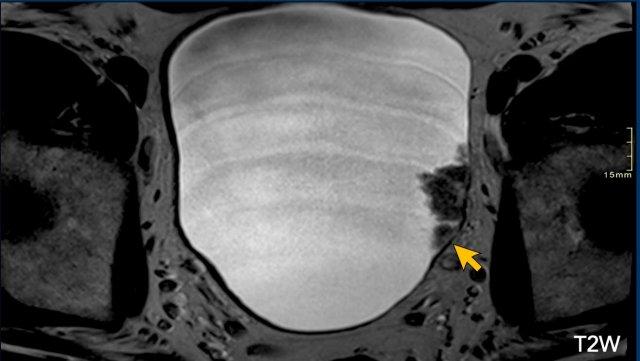

Có một tổn thương dạng u nhú có cuống ở thành bàng quang bên trái vùng sau-bên.

Đường kính tổn thương > 1 cm.

Lớp cơ còn toàn vẹn hoàn toàn (Điểm T2W: 2).

Phía sau tổn thương này, có một tổn thương nhỏ thứ hai được chỉ bởi mũi tên (Điểm T2W: 1).

Tiếp tục xem hình ảnh DCE…